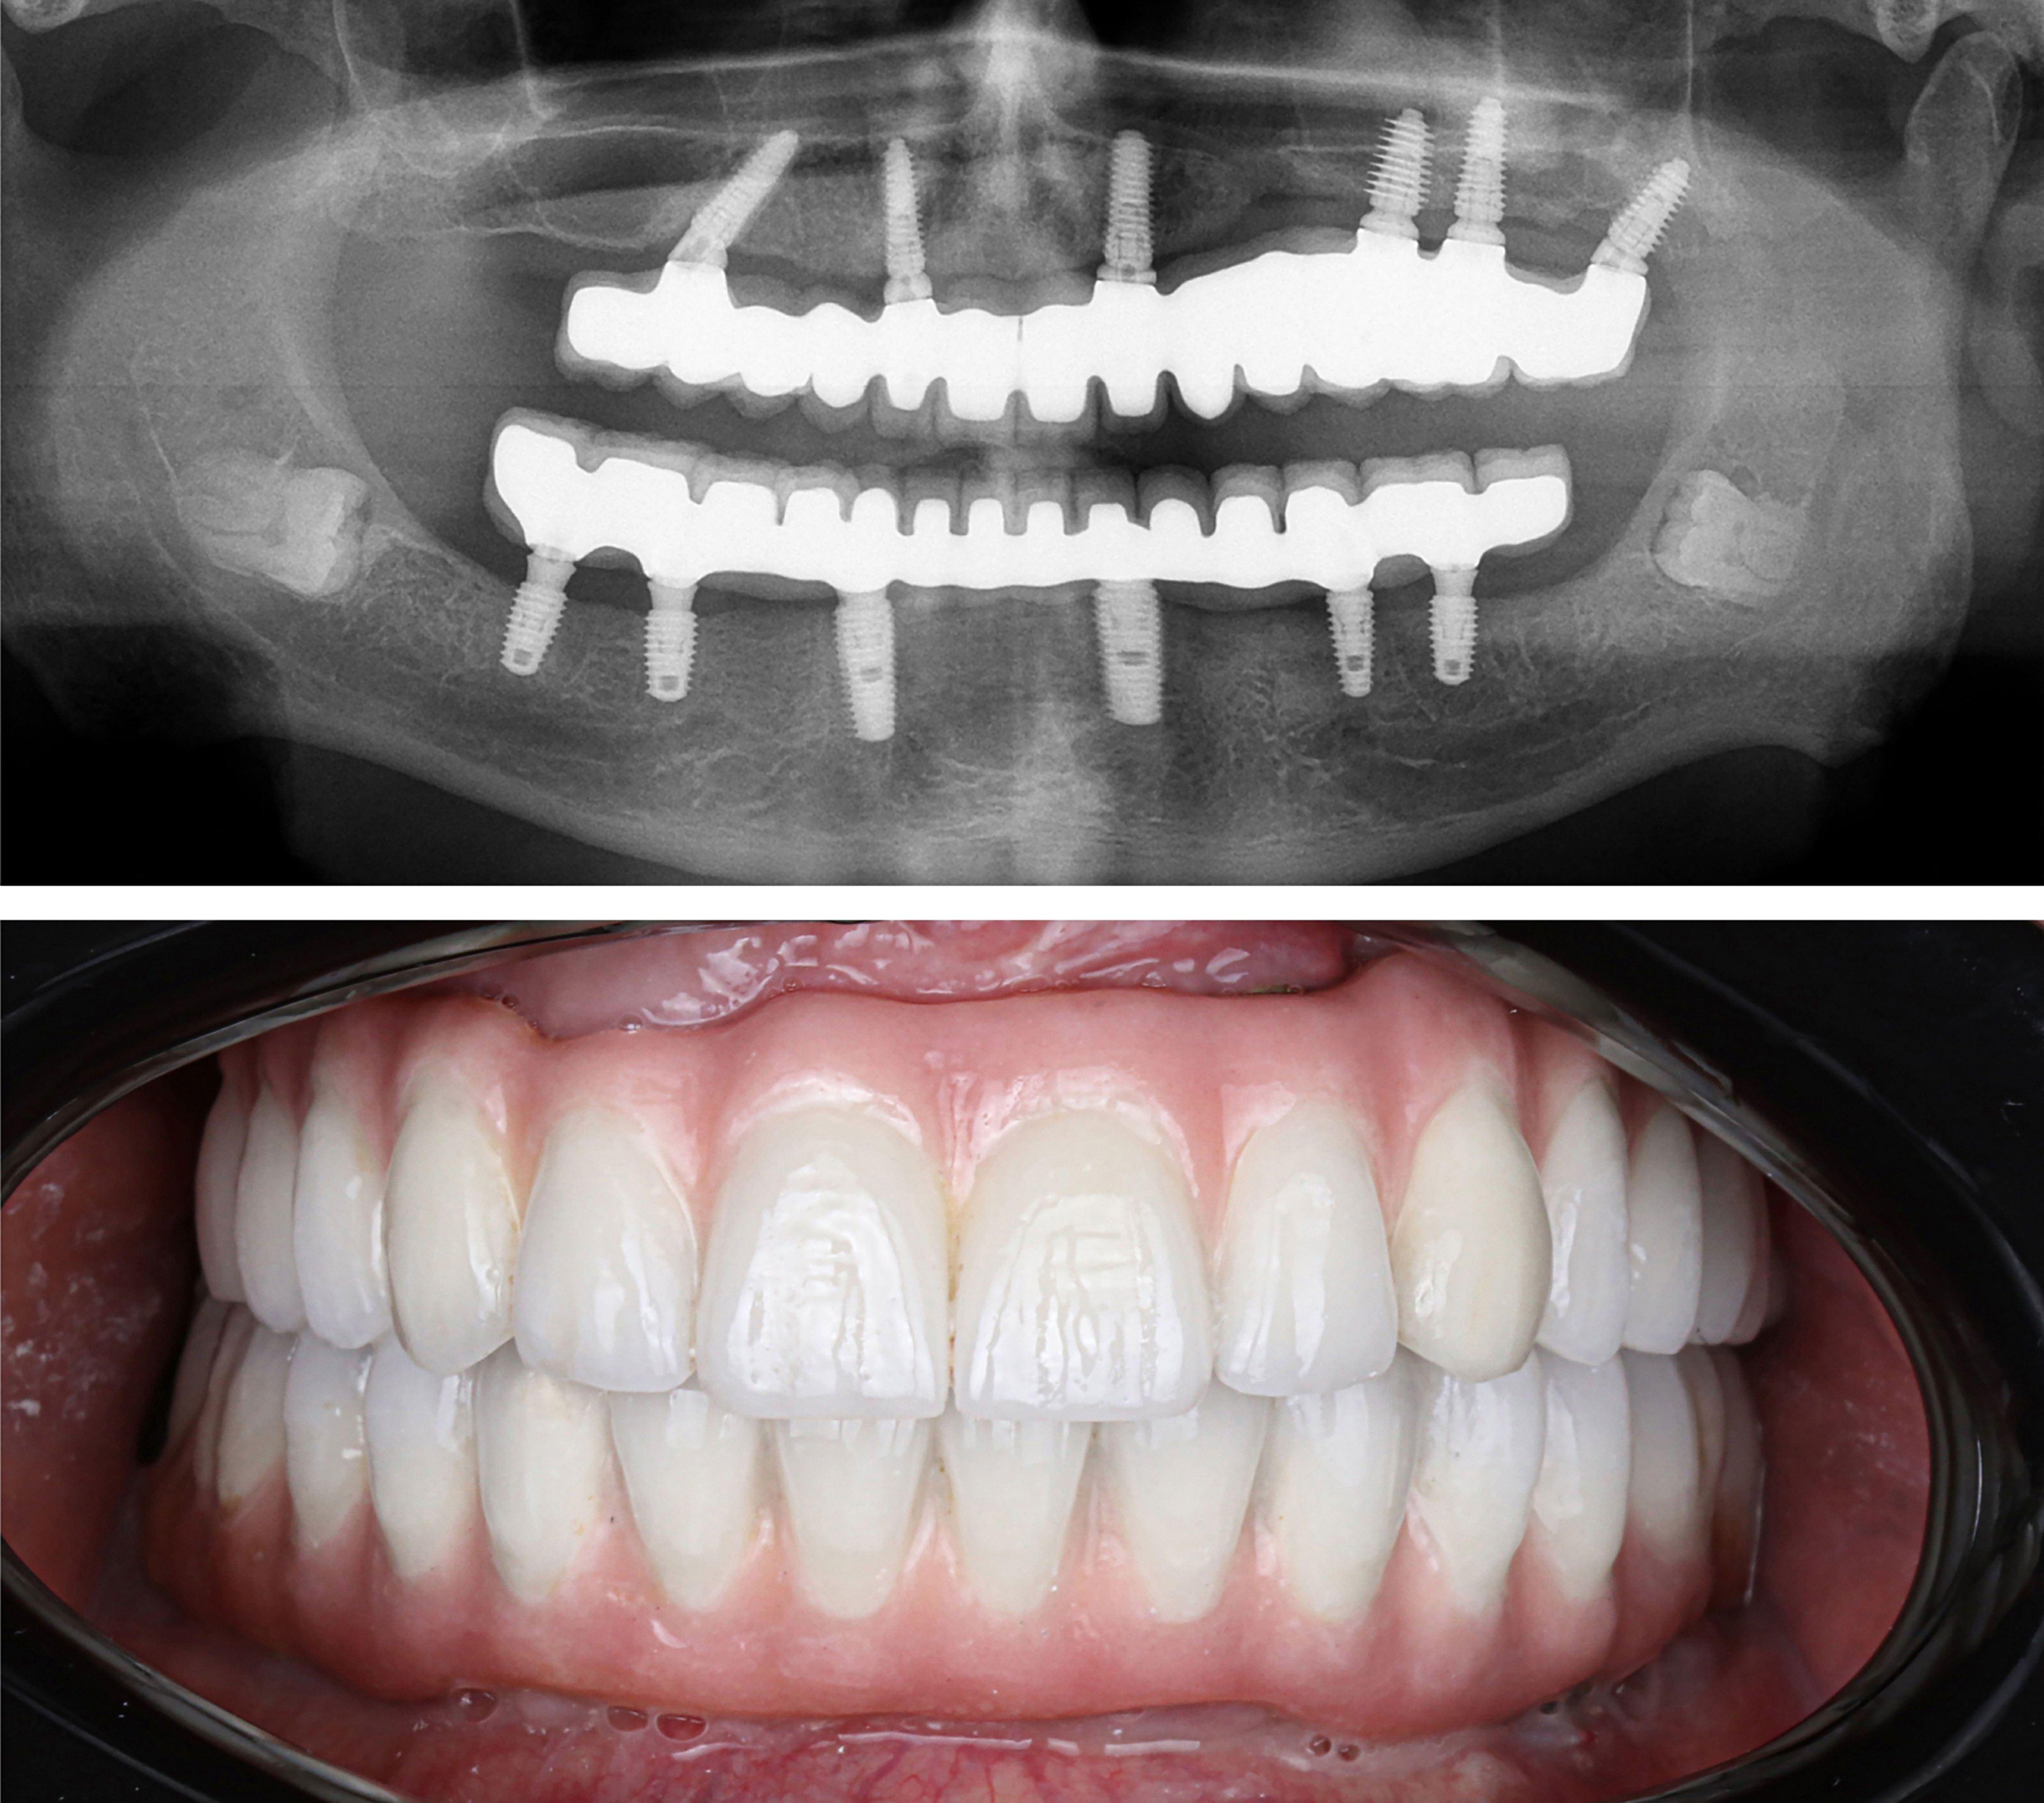

Example transformations achievable with dental implants

Includes everything from start to finish. No hidden fees.

Includes surgical placement of 4 to 8 implants.

In certain cases, extra pterygoid implants may be placed in the upper jaw by our oral surgeons to provide added strength and support for your zirconia teeth. ($6000 Value)

Includes healing teeth within 24 hours of procedure.

Before your final zirconia teeth are secured, you’ll wear a try-in set for two weeks. This ensures your comfort, bite, and smile look exactly right before moving forward.

Final ultra aesthetic zirconia fixed teeth.